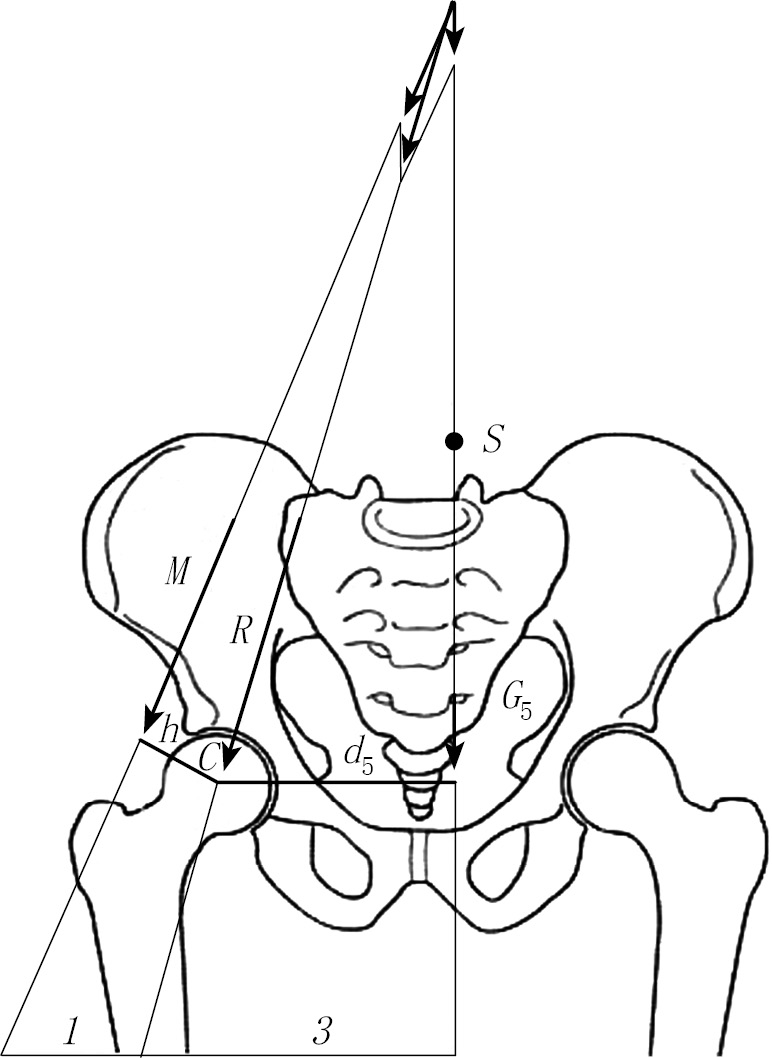

A completely different picture is seen when a person is standing on one limb. In this case, the hip joint retains a partial body weight (head + body + two arms + leg weight in the step transfer position). When single-support standing, muscle forces act that prevent the pelvis from tipping over (Fig. 2).

Fig. 2. Schematic representation of the load on the hip joints when a person is standing on the right limb (according to Pouwels)

In this case, the leverage system operates by the equation of vectors: hMr = d5G5t. Point S of the vertically acting partial body weight G5 is shifted to the side of the leg, which is in the transferable period of the step. The lever of the person’s load arm is d5. On the side of the leg on which the person stands, the resulting M (abductor forces) acts with a lever arm of size h. For this reason, the partial weight of the body G5 on the side of the leg in the position of the transferable period of the step causes a moment of rotation around the femoral head (d5G5t), and it is counteracted by the moment of rotation of the muscular strength of the contralateral side (hMr). As a result, a system of balancing levers is formed: hMr = d5G5t. Pauwels found that the lever arm d5 is three times longer than the lever arm h of muscle strength M. As a result, the muscle strength of the abductors must be three times greater in order to maintain body balance. The resulting R should be approximately four times greater than the partial bodyweight of G5.

Pauwels performed similar calculations not only on healthy joints but also with coxa valga. The author concluded that with an increase in the collum-diaphyseal angle, the value of the total resulting R increases, which entails an increase in the load on the joint.